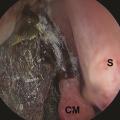

L’examen endoscopique de la fosse nasale doit être réalisé en urgence devant toute suspicion clinique. Il recherche un aspect atone, voire nécrotique, des muqueuses, typique des mucormycoses (fig. 5). Il permet de confirmer le diagnostic, par la réalisation de biopsies pour analyses mycologiques et anatomopathologiques. L’examen direct mycologique réalisé en urgence avec un microscope à fluorescence peut établir le diagnostic en identifiant les filaments mycéliens évocateurs. L’examen anatomopathologique retrouve des filaments larges, non septés, associés à un infiltrat fongique périnerveux, avec une réponse inflammatoire neutrophilique et surtout des images d’angio-invasion fongique avec thrombose et nécrose (fig. 3). La culture mycologique est négative dans plus de la moitié des cas dans une série française.4 La PCR Mucorales sur les biopsies et sur prélèvement sanguin peut être une aide au diagnostic puis dans le suivi.6,7